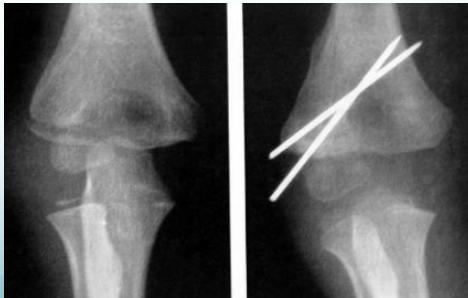

Lateral Condyle - Humerus

- Mostly cartilaginous

- Intra-articular fracture

- Fracture easily missed

- Displacement not appreciated/underestimated

- Needs fixation even if undisplaced

- Treatment: reduction, K-wire, slab

- If not fixed, may displace